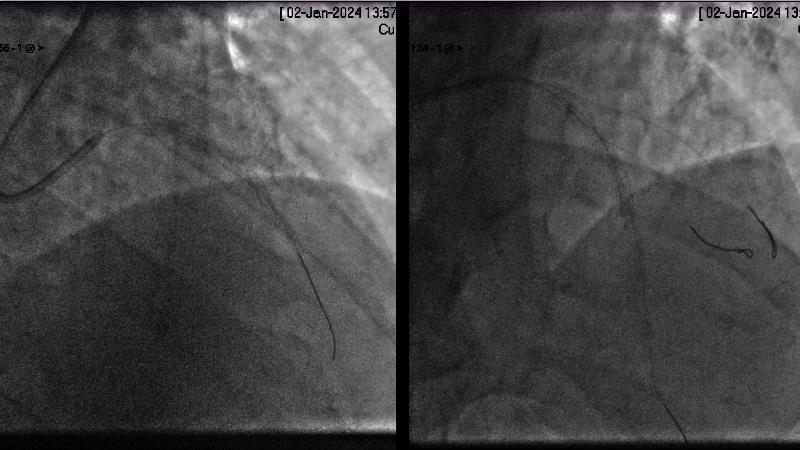

Browse this EuroPCR 2024 session to explore the safety and efficacy of sirolimus-coated balloons from pre-clinical data, review MagicTouch data from real-world populations with case-based examples, and learn about the MagicTouch sirolimus-coated balloon clinical programs. Discover insights and takeaways from the significance of the EASTBOURNE subgroups, and analyze the challenges and opportunities in PCI for diabetic patients.